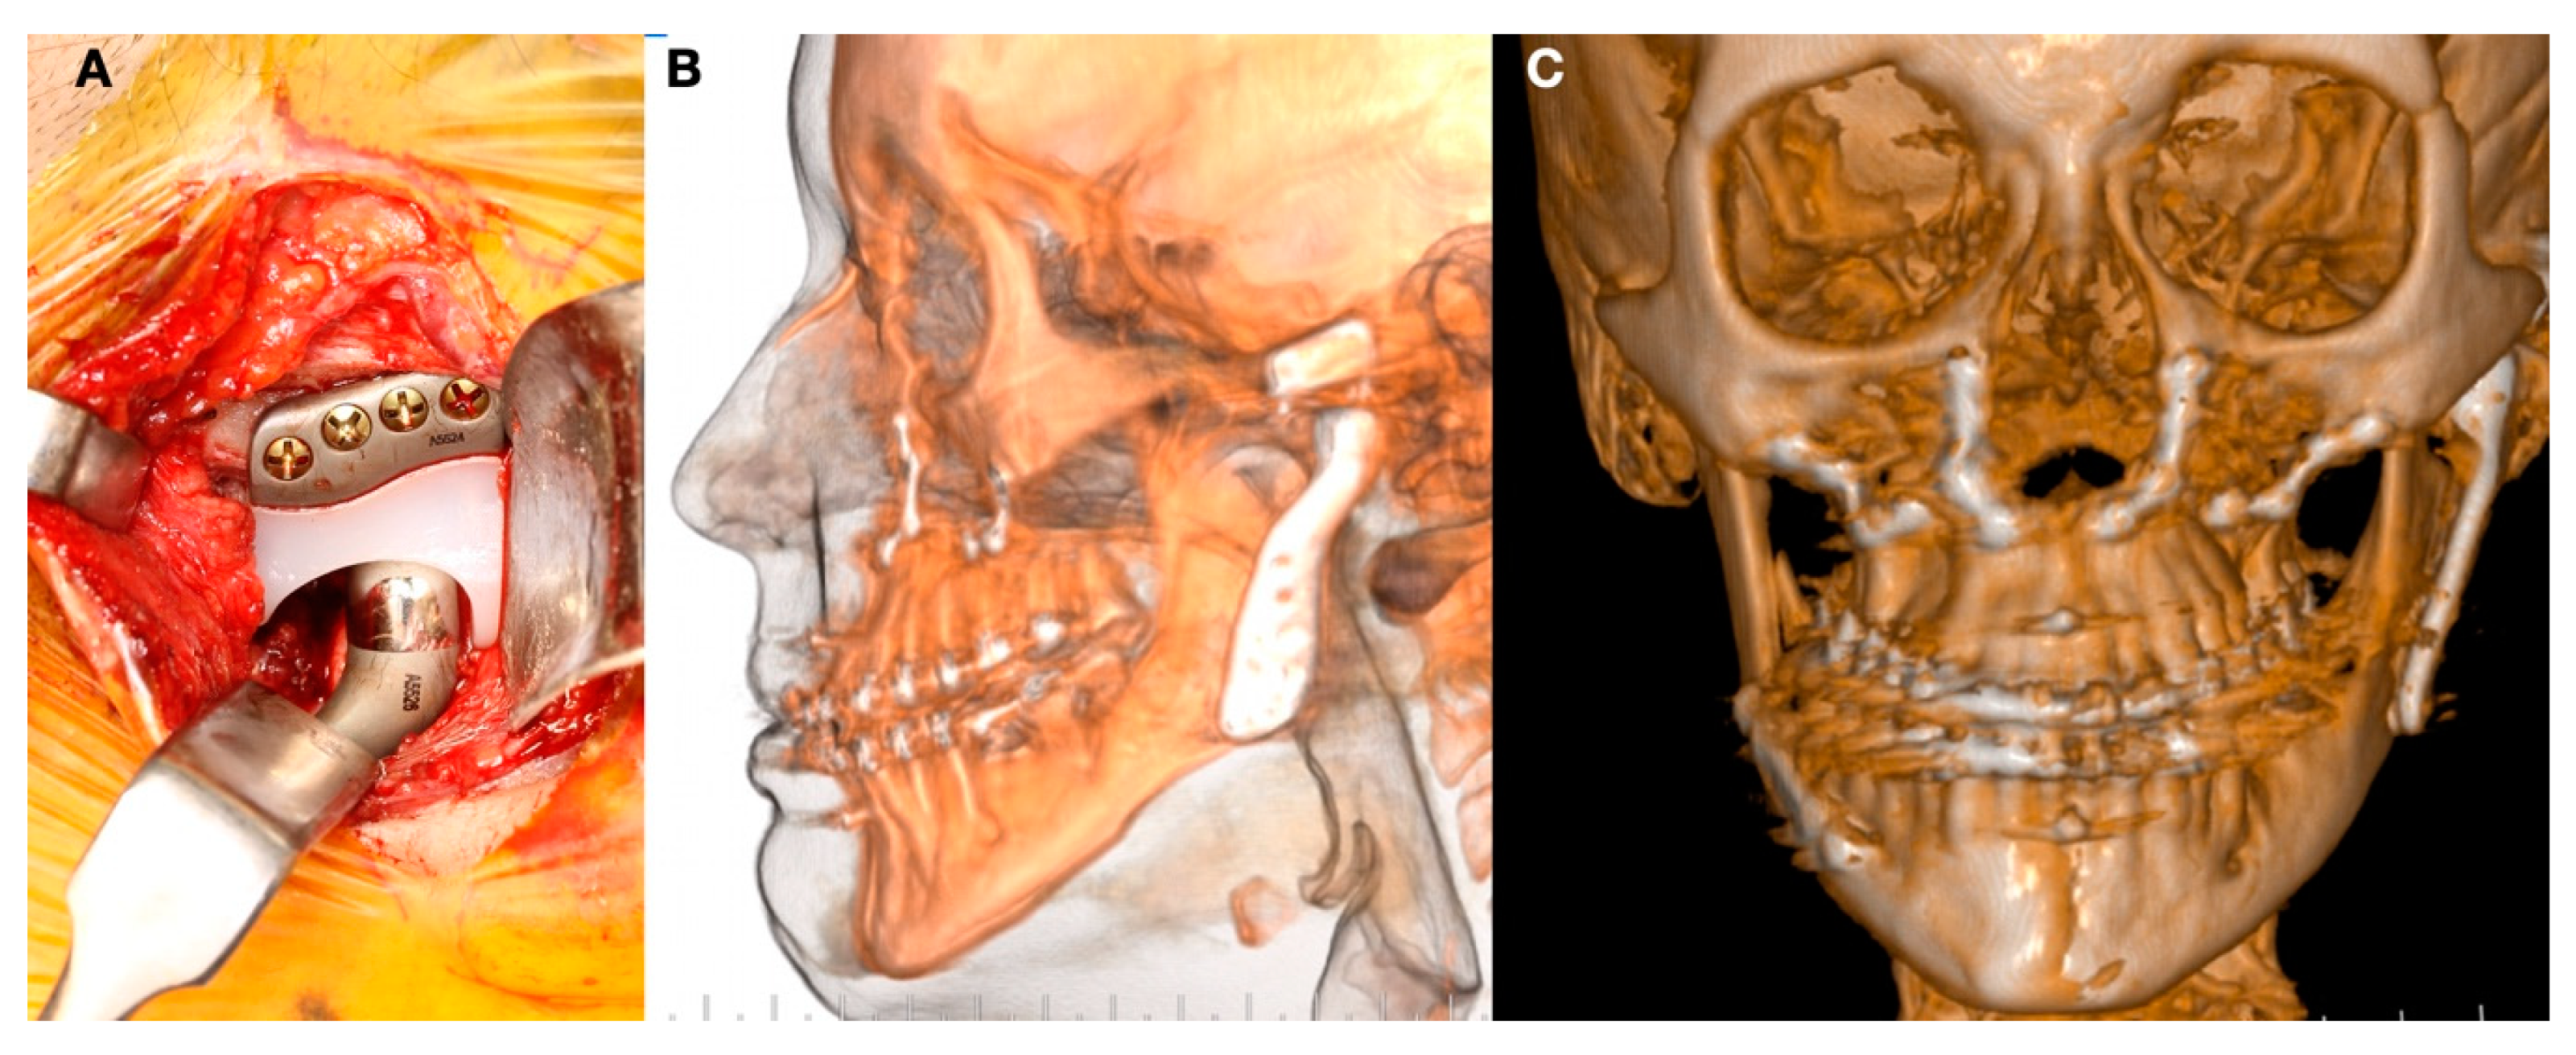

- Malformations, Pathology, or Trauma of the Mandibular Condyle